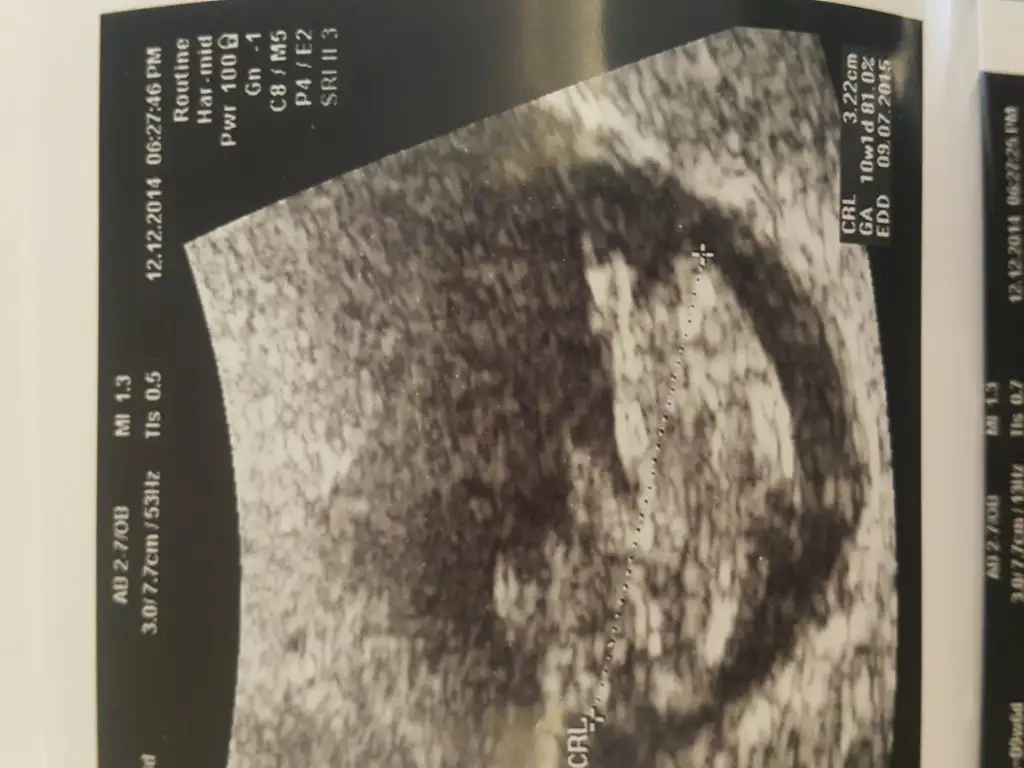

Gunaydin arkadaslar.dun kontrolum vardi.9+4 olmaliydim .10+1 misim.cok merak ediyorum melegimin cinsiyetini.yorumlarsaniz duaciniz olurum

allah gönlüne göre versin bana öyle geldi du i daha bakayımAy cidden mi![]()

Âmin isteyen herkese versin inş. Bak bakimallah gönlüne göre versin bana öyle geldi du i daha bakayım

baktım ama popodaki + işaretinin olduğu yere nub dersek kız gibi, başka çıkıntı göremedim. senin de kafanı karıştırıyoruz bi kız bi erkek diye ama..![]()